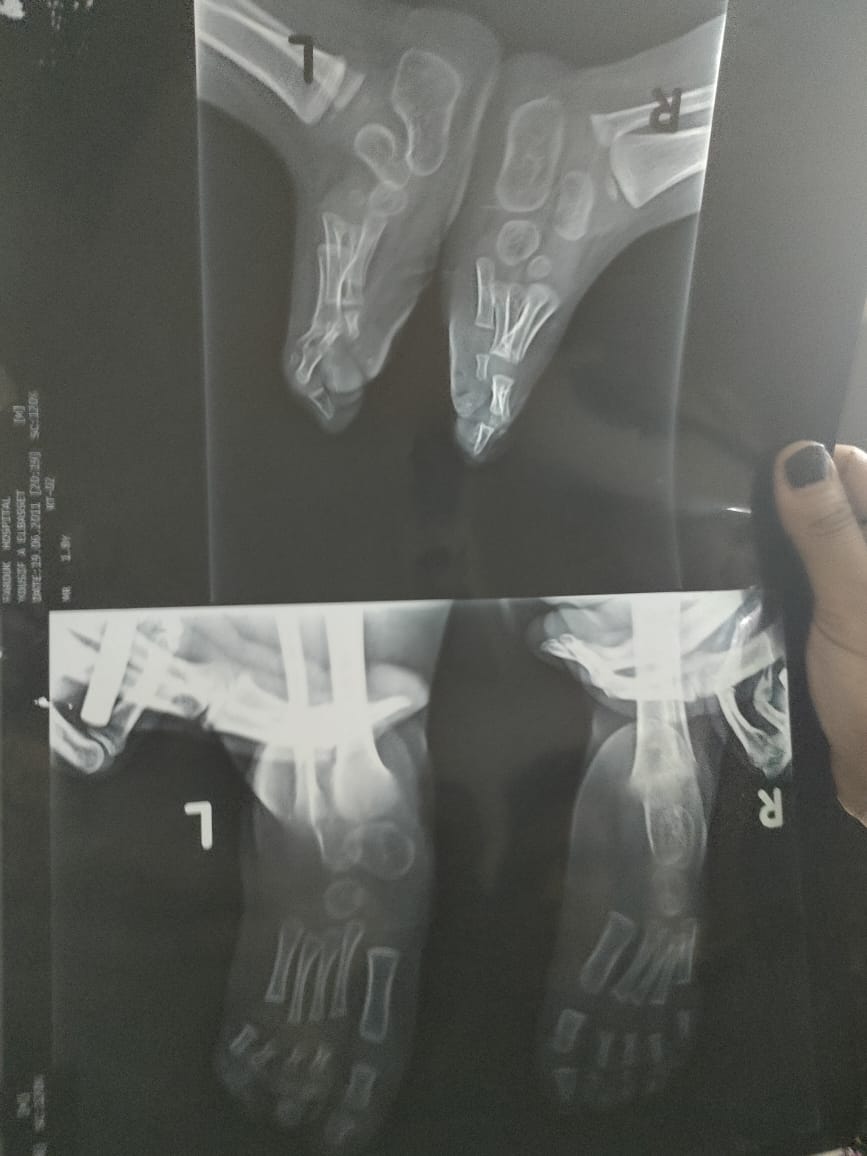

يعاني الطفل يوسف عبد الباسط الذي يبلغ 11 عاما بمنطقة الملقة بدار السلام في محافظة القاهرة، منذ ولادته في عام 2009 من عيب خلقي “ضمور في القدمين”، مصحوبا بعدم وجود النخاع الشكوى للطفل، بالإضافة إلى ثقبين في القلب، فلم يترك والد الطفل ابنه وقام بعرضه على الأطباء، والذين أكدوا أنه يحتاج إلى السفر خارج مصر لإجراء عمليه تصل تكليفها إلى أكثر من 500 ألف جنيه.

والتقى “القاهرة 24”، بوالد الطفل ويدعى عبد الباسط رمضان، وقال: “بعد ولادة طفلي مباشرة كان يعاني من عيب خلقي واعوجاج في القدمين، فتوجهنا به لأحد الأطباء، وتم إجراء الأشعة وتبين أنه يعاني من عيب خلقي وهو ضمور في القدمين، بالإضافة إلى وجود ثقبين بالقلب”.

وتابع: "ذهبنا به لمركز الأشعة وأكدوا لنا أن هذا عيب خلقي، وقمنا بالبحث عن الأطباء المتخصصين ذو الخبرة والكفاءة حتى نستطيع معالجته، ونجحت إحدى العمليات التي تم إجراءها في قدميه وهي شد أوتار تصل إلى 3000 جنيه في الجلسة، و بعد معاناة استطاعوا أن يقوموا قدميه المعوجتين، وابني يعاني أيضا من مشكلة التبول والتبرز وتم إجراء الأشعة وعمل عملية توسيع باءت بالفشل نظرا لأن الطفل يحتاج إلى نخاع شوكي، وقمت ببيع التاكسي الخاص بي حتي استطيع معالجة ابني ولكن العمليات التي يحتاج أكثر من 500 ألف جنيه خارج مصر".